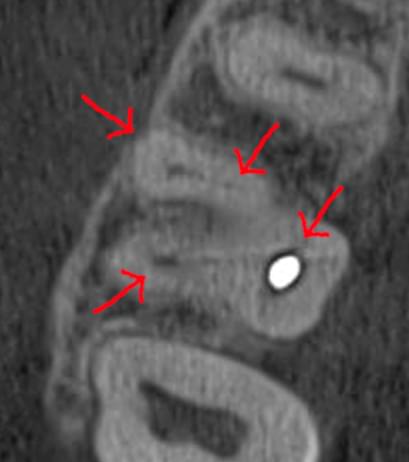

При плануванні імплантації лікарю важливо знати дві речі: об'єм кістки та точне розташування нервів.

КТ дозволяє провести віртуальну операцію: встановити імплант у програмі, виключивши будь-які ризики травмування пацієнта.